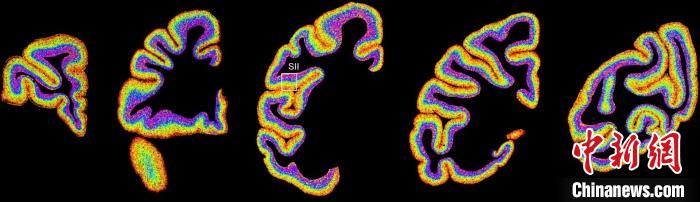

圖為不同類型細(xì)胞在獼猴大腦上的分布切片?!≈袊?guó)科學(xué)院腦科學(xué)與智能技術(shù)卓越創(chuàng)新中心 供圖

李澄宇說(shuō),科研人員做的事情好似“查戶口”,也就是搞明白猴腦里有哪些細(xì)胞、這些細(xì)胞在哪些位置。搞明白這些就形成了一個(gè)大的數(shù)據(jù)集,科研團(tuán)隊(duì)挖掘這個(gè)數(shù)據(jù)集,發(fā)現(xiàn)了很多有意思的現(xiàn)象:比如,興奮性神經(jīng)元、抑制性神經(jīng)元以及非神經(jīng)元在大腦皮層中的分布呈現(xiàn)明顯的特異性,也就是不同細(xì)胞“住”哪,有一定規(guī)律。